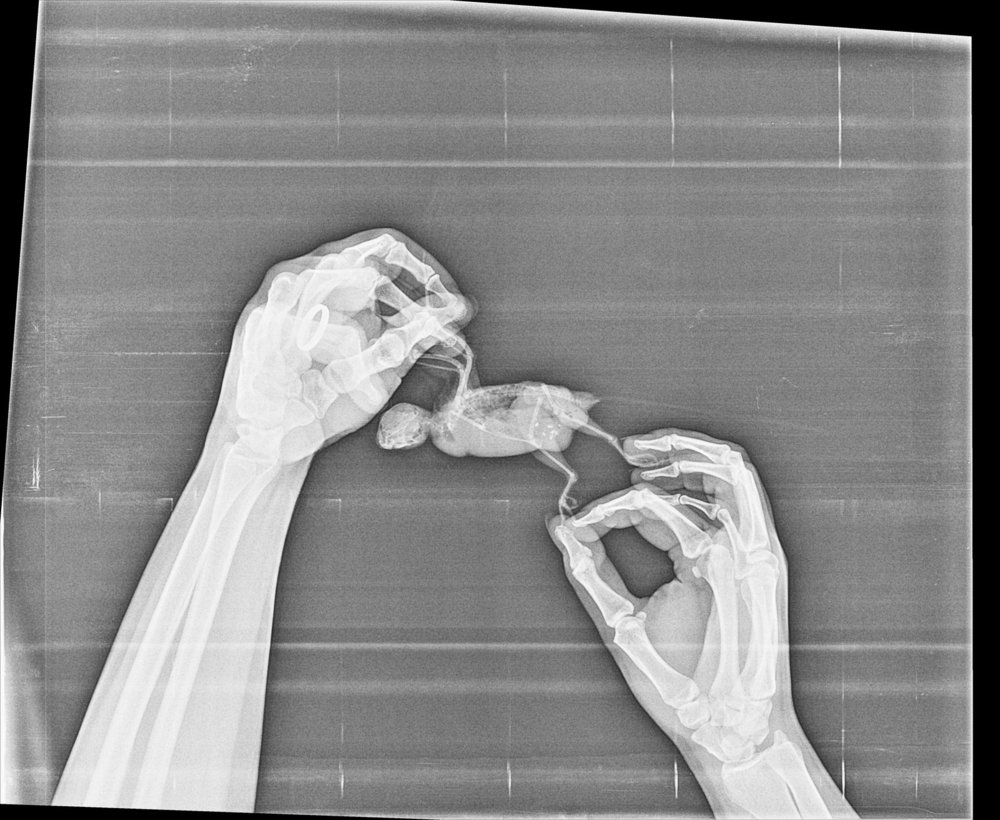

Данечка:) Опубликовано 22 апреля, 2020 Автор #2 Опубликовано 22 апреля, 2020 @Данечка:) Сделали рентген, надеюсь, читабельный. Сегодня птиц активнее, сам кушает и кашу и корм, играет с игрушками, болтает. Помет нормального цвета, правда все равно с водой. Нам советовали начать с пробиотиков, раз проблема ЖКТ есть, но ещё ничего не давала. @Zosia, полагаюсь на Ваш опыт и Вашу помощь. Заранее спасибо!

Zosia Опубликовано 25 апреля, 2020 #35 Опубликовано 25 апреля, 2020 Я вам ответила в личку. Вы уже сделать ничего не могли. Рентген Дани я помещу в свой список онкопациентов